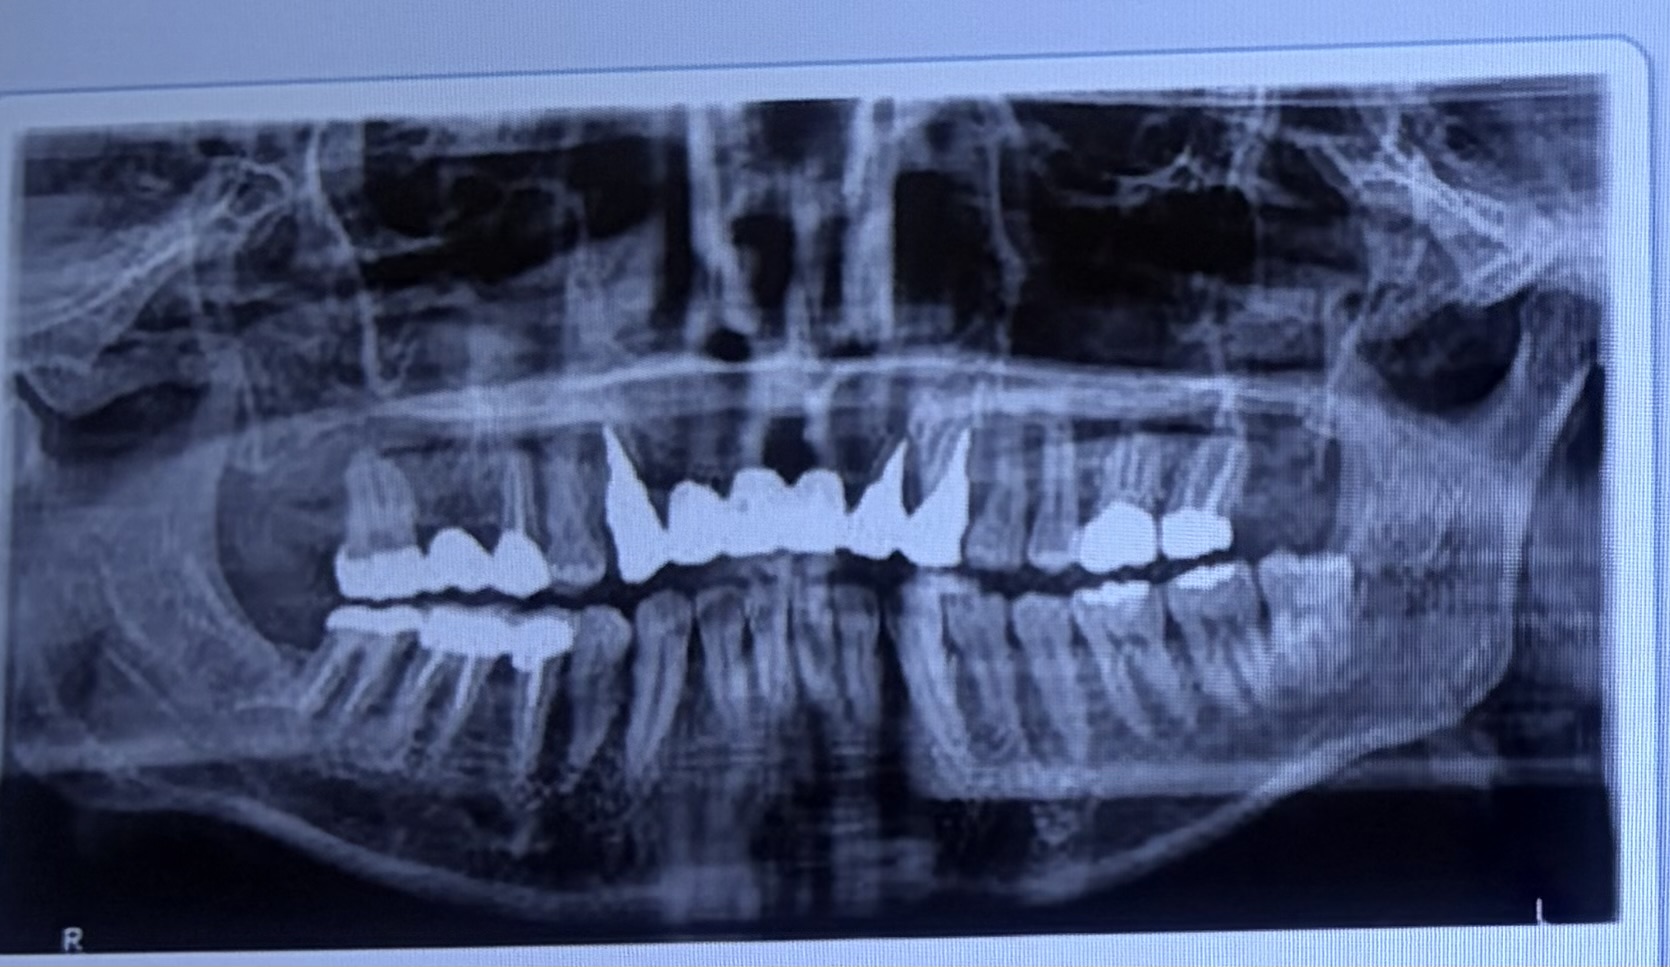

ブリッジをしている歯に膿と痛みがあります。抜歯せずに治療できますか?

ブリッジの支台歯に膿が溜まりました。抜歯せずに治療はできますか?

前歯のブリッジがグラついています。抜歯しかないでしょうか?